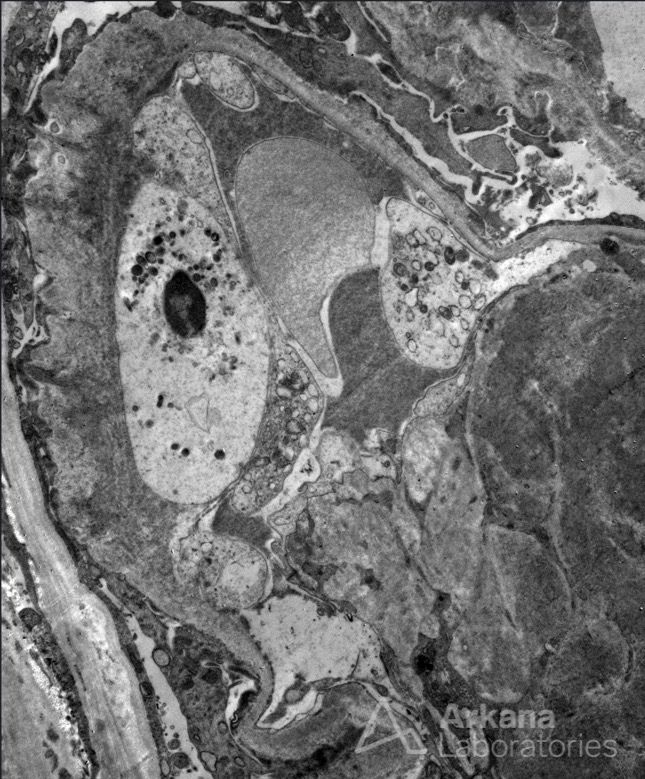

MD at CHU de Lille, France. Member of INSERM UMR S1172. Special interest in kidney.